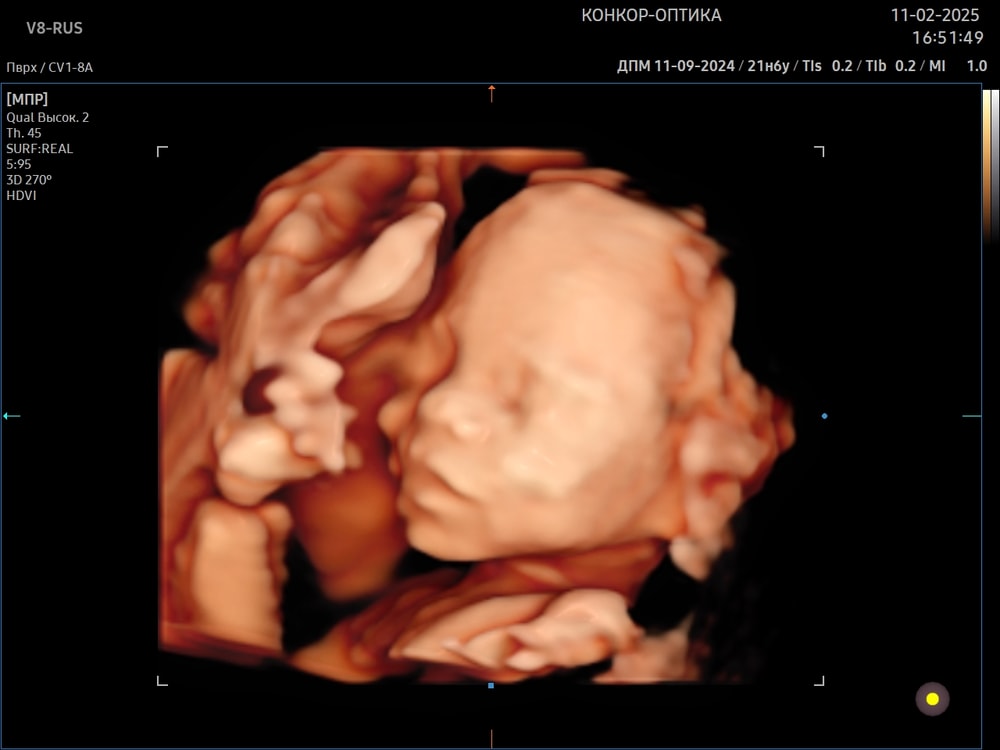

Делала в 28+4 , отлично удалось поймать личико